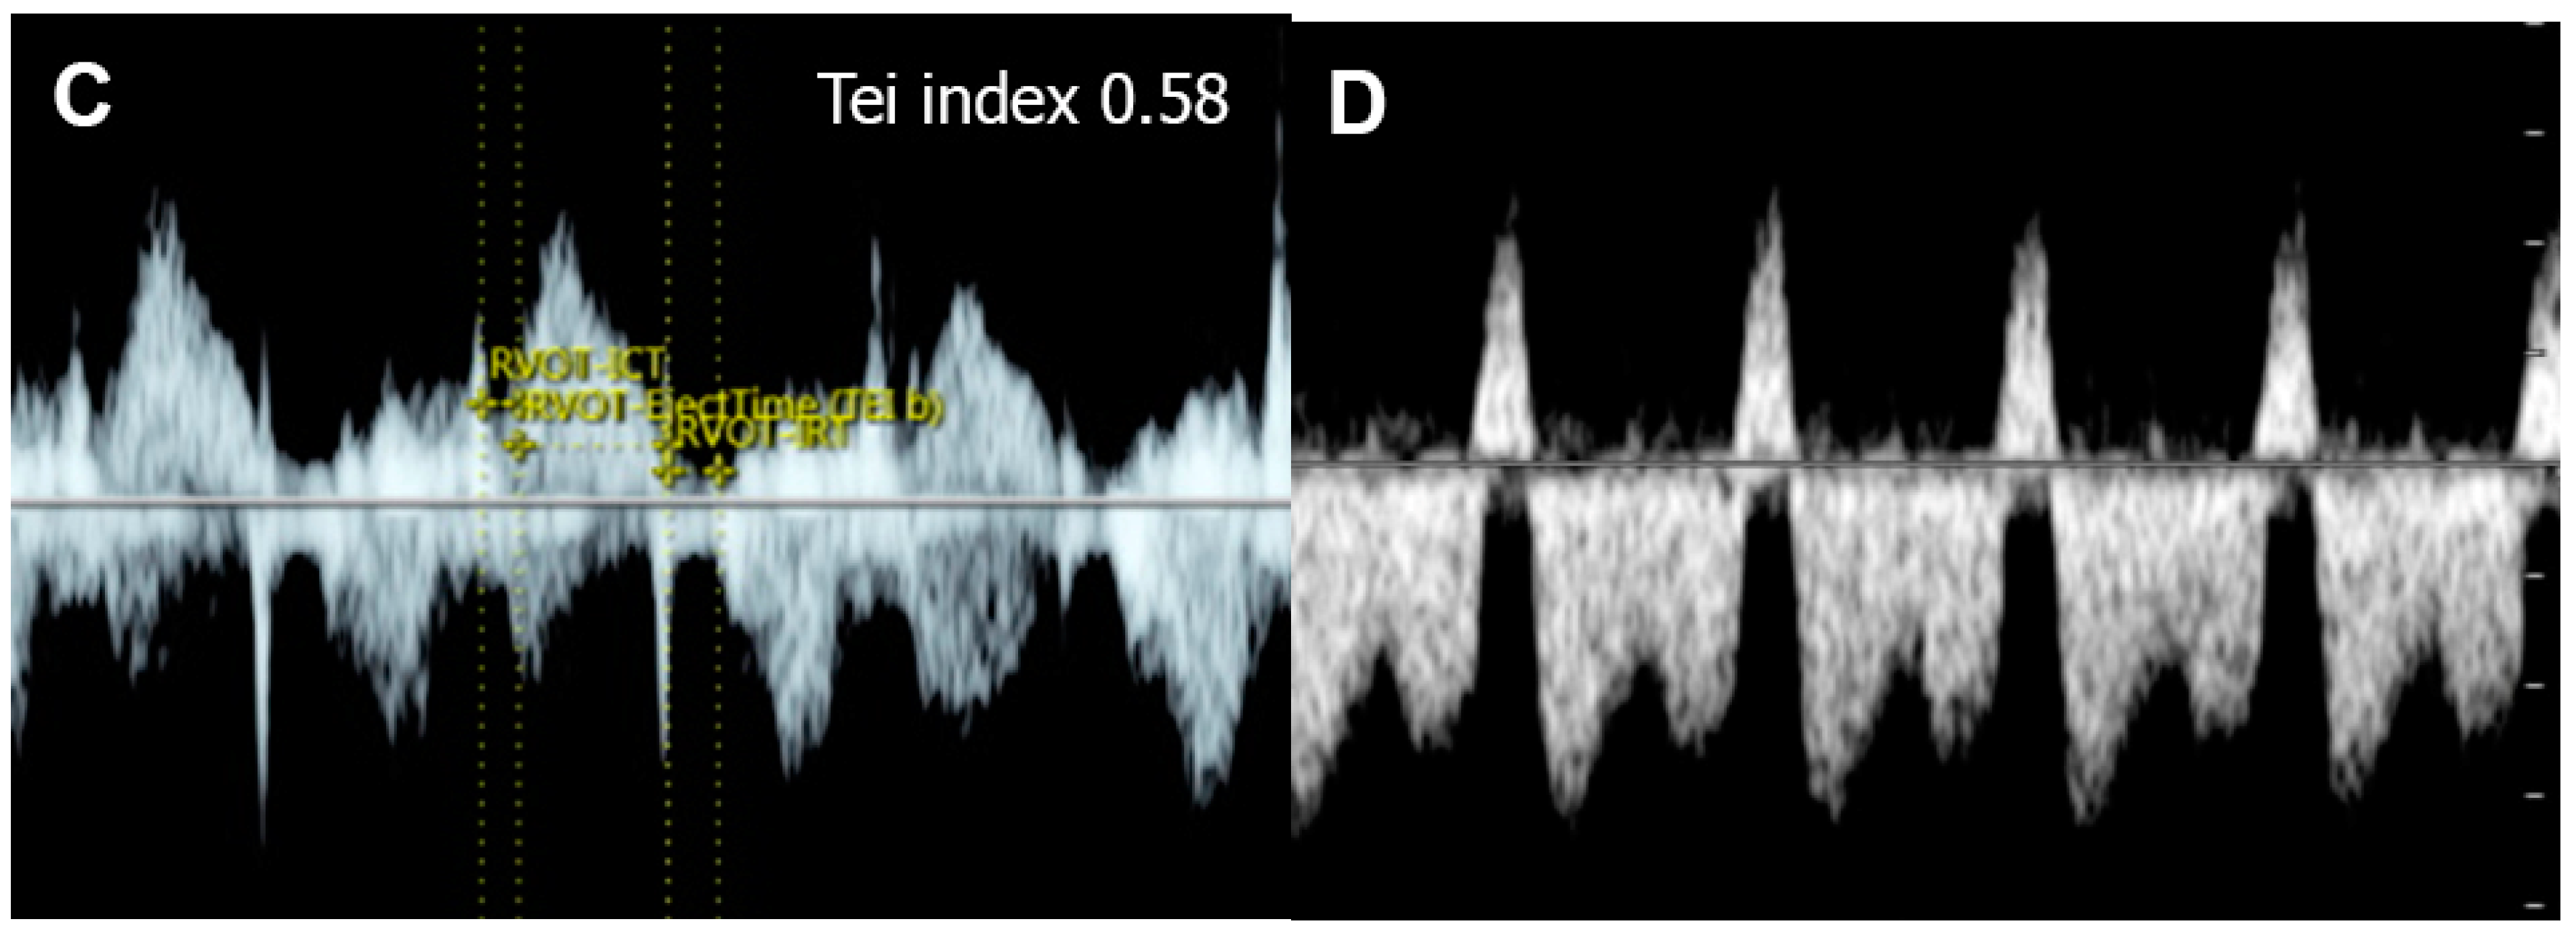

| Parameters | Abnormal Changes | Interpretation |

|---|---|---|

| Performance | ||

| Shortening fraction | Decreased (<28%) | Systolic dysfunction |

| Increased | Reduced afterload/increased contractility | |

| Ejection fraction | Decreased <50%) | Systolic dysfunction |

| Cardiac output (Stroke volume) | Decreased (Z < −2) | Systolic dysfunction/poor filling |

| Increased (Z > +2) | Reduced afterload/volume load | |

| Tei index | Increased > 0.50 | Global cardiac dysfunction |

| ICT: 28 (22–33) ms | Prolonged | Systolic dysfunction |

| IRT: 34 (26-41) ms | Prolonged | Diastolic dysfunction |

| Systolic strain/Strain rate | Increased | Reduced afterload |

| Decreased | Reduced contractility | |

| E/Vp (Color M-mode) | Increased | Diastolic dysfunction |